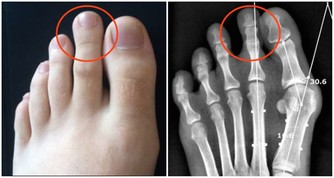

小腿和腳趾的抽筋小腿和腳趾是抽筋多發的部位,如果發生抽筋可立即進行如下操作:自己坐在地上,膝蓋彎曲90度左右,雙手握住前腳掌或者抽筋一側腳的大腳趾並將其扳向自己身體的方向,持續時間大約20秒,重複2-3次,可視肌肉痙攣緩解情況適當增加次數。